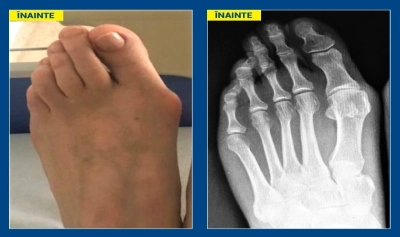

Cum poate fi evitată recidiva monturilor piciorului după intervenția chirurgicală?11-11-20201.103Sănătate